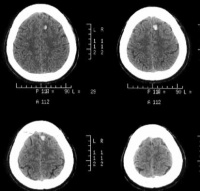

脑挫裂伤

颅内血肿

对脑挫裂伤与脑震荡可以作出明确的鉴别诊断,并能清楚地显示脑挫裂伤的部位、程度和有无继发损害,如出血和水肿情况。同时,可根据脑室和脑池的大小、形态和移位的情况间接估计颅内压的高低。尤为重要的是,对一些不典型的病例,可以通过定期CT扫描,动态地观察脑水肿的演变或迟发性血肿的发生。近年来,在有此设备的医院CT已作为急性头伤的常规检查,因为单靠伤史和查体难以作出超早期诊断。Stein等(1990)指出在GCS13~15危害较小的轻型头

伤中,首次CT的阳性发现率竟占18%,并有5%需行手术治疗,强调早期CT检查的必要性。